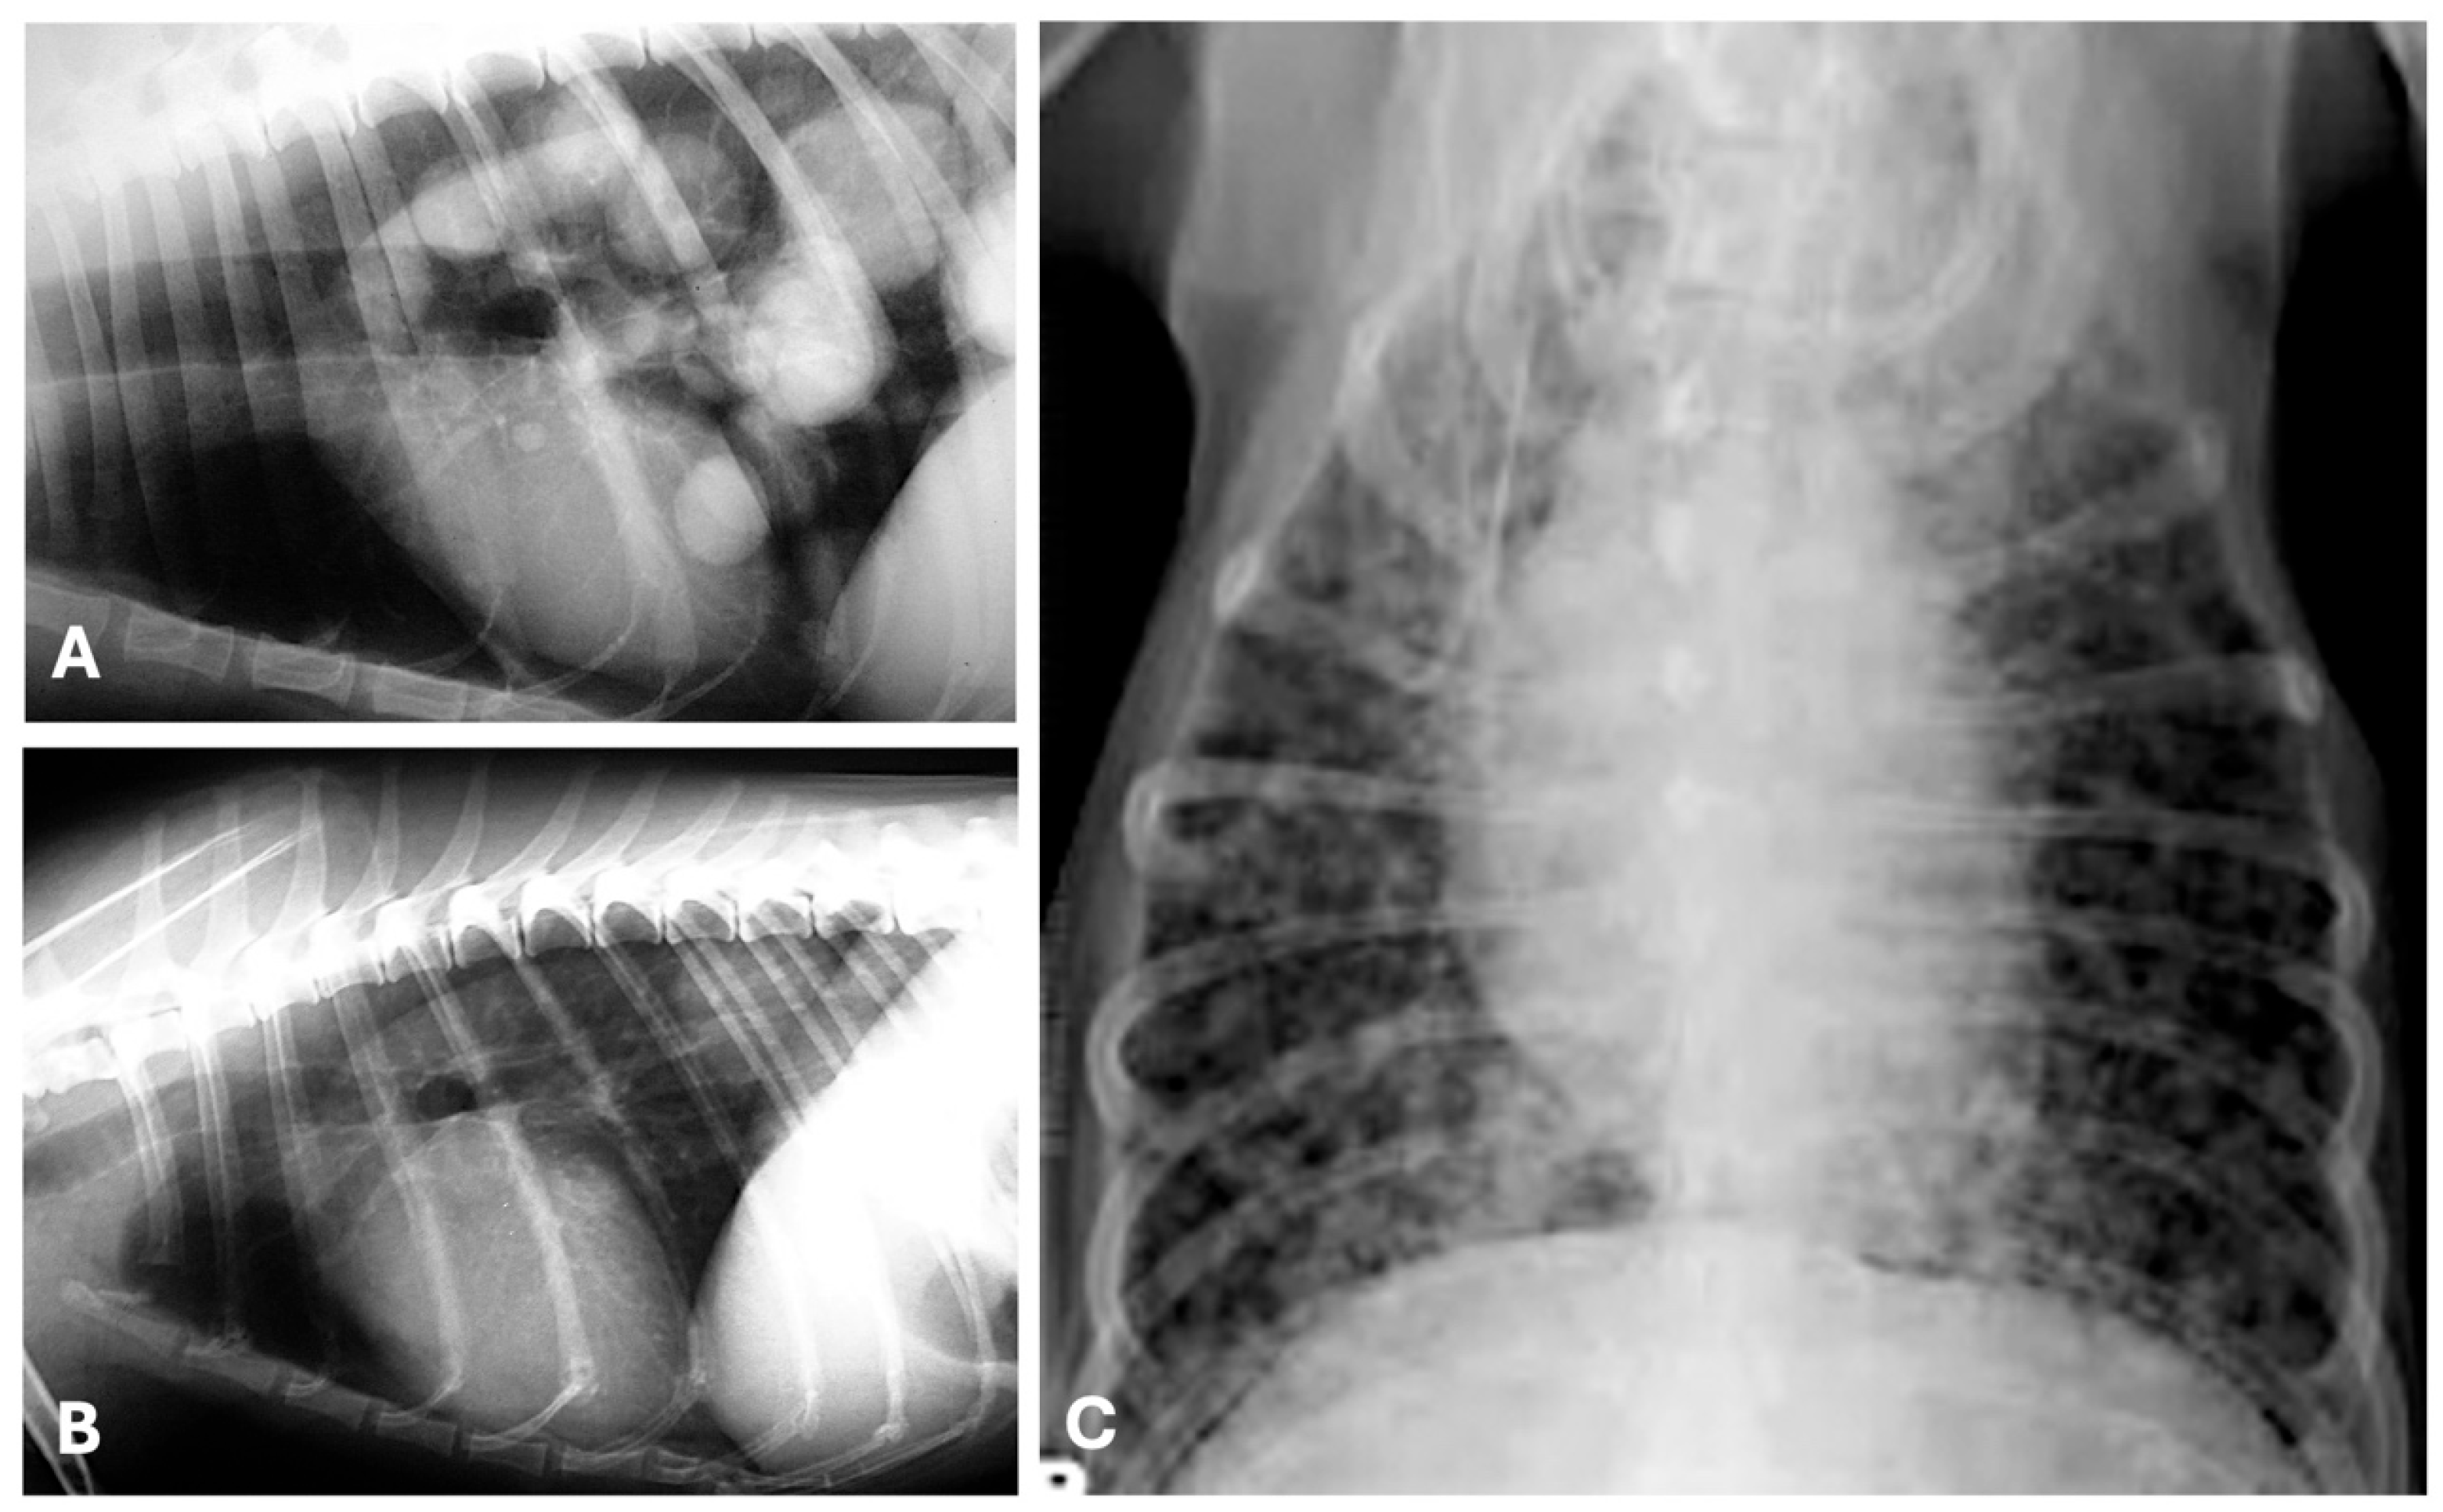

4.1. Radiography

- Forrest, L.J.; Graybush, C.A. Radiographic Patterns of Pulmonary Metastasis in 25 Cats. Vet. Radiol. Ultrasound 1998, 39, 4–8. [Google Scholar] [CrossRef]